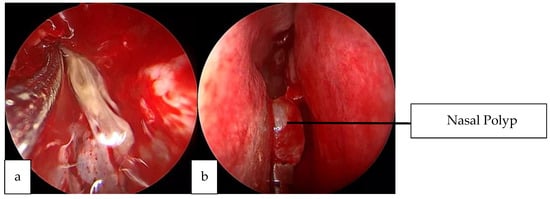

2.2. Case 2